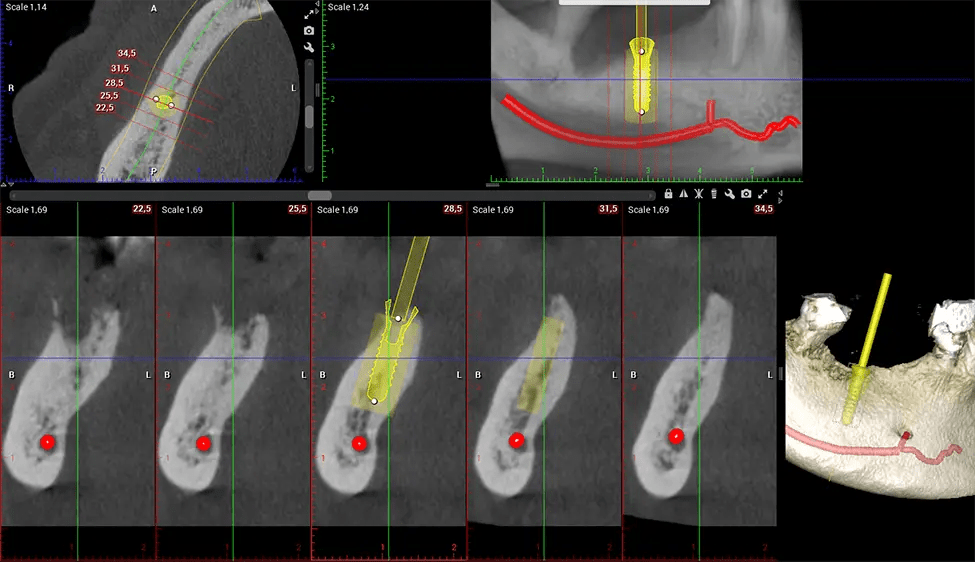

When paired with extractions, dental implant placement, or bone grafting, CBCT technology can provide you with a quicker and much more comfortable experience. This is because the 3D image provides a more detailed picture of your entire oral cavity, allowing your dentist to walk you through each step of the process before it occurs. This often helps patients feel more prepared and comfortable overall, especially if they have had a traumatic experience with past dental treatments.

After the scanning process, the captured X-ray images are processed by the CBCT software, which applies algorithms to reconstruct a detailed 3D image of the scanned area. The software compiles these individual X-ray images and creates a digital 3D representation of the patient’s anatomy. The reconstructed 3D CBCT image can be viewed and analyzed by the dentist or radiologist. This image can be manipulated, rotated, and zoomed in or out to examine specific structures and evaluate the patient’s condition.

Our patented SCARA technology enables doctors to capture True Extraoral Bitewings that are as accurate at detecting caries as a 2D bitewing series, but with half the radiation dose. With our bitewings, doctors can view the apices of teeth on both jaws providing a more comprehensive view of the patients’ anatomy.